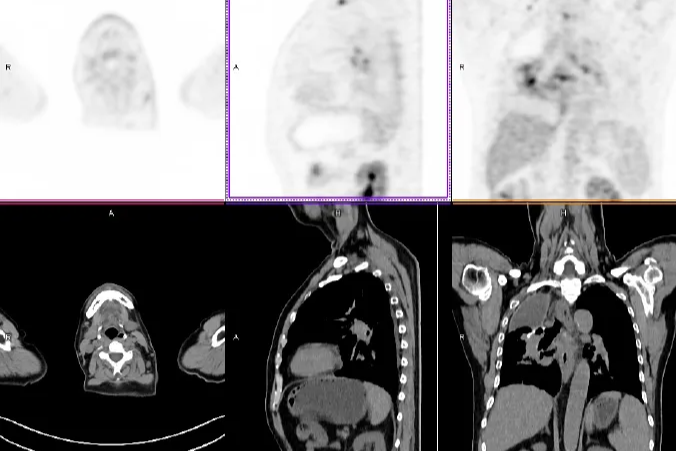

「牵一发而动全身」—以为是肺的事,PET/CT 揭秘—全身淋巴瘤